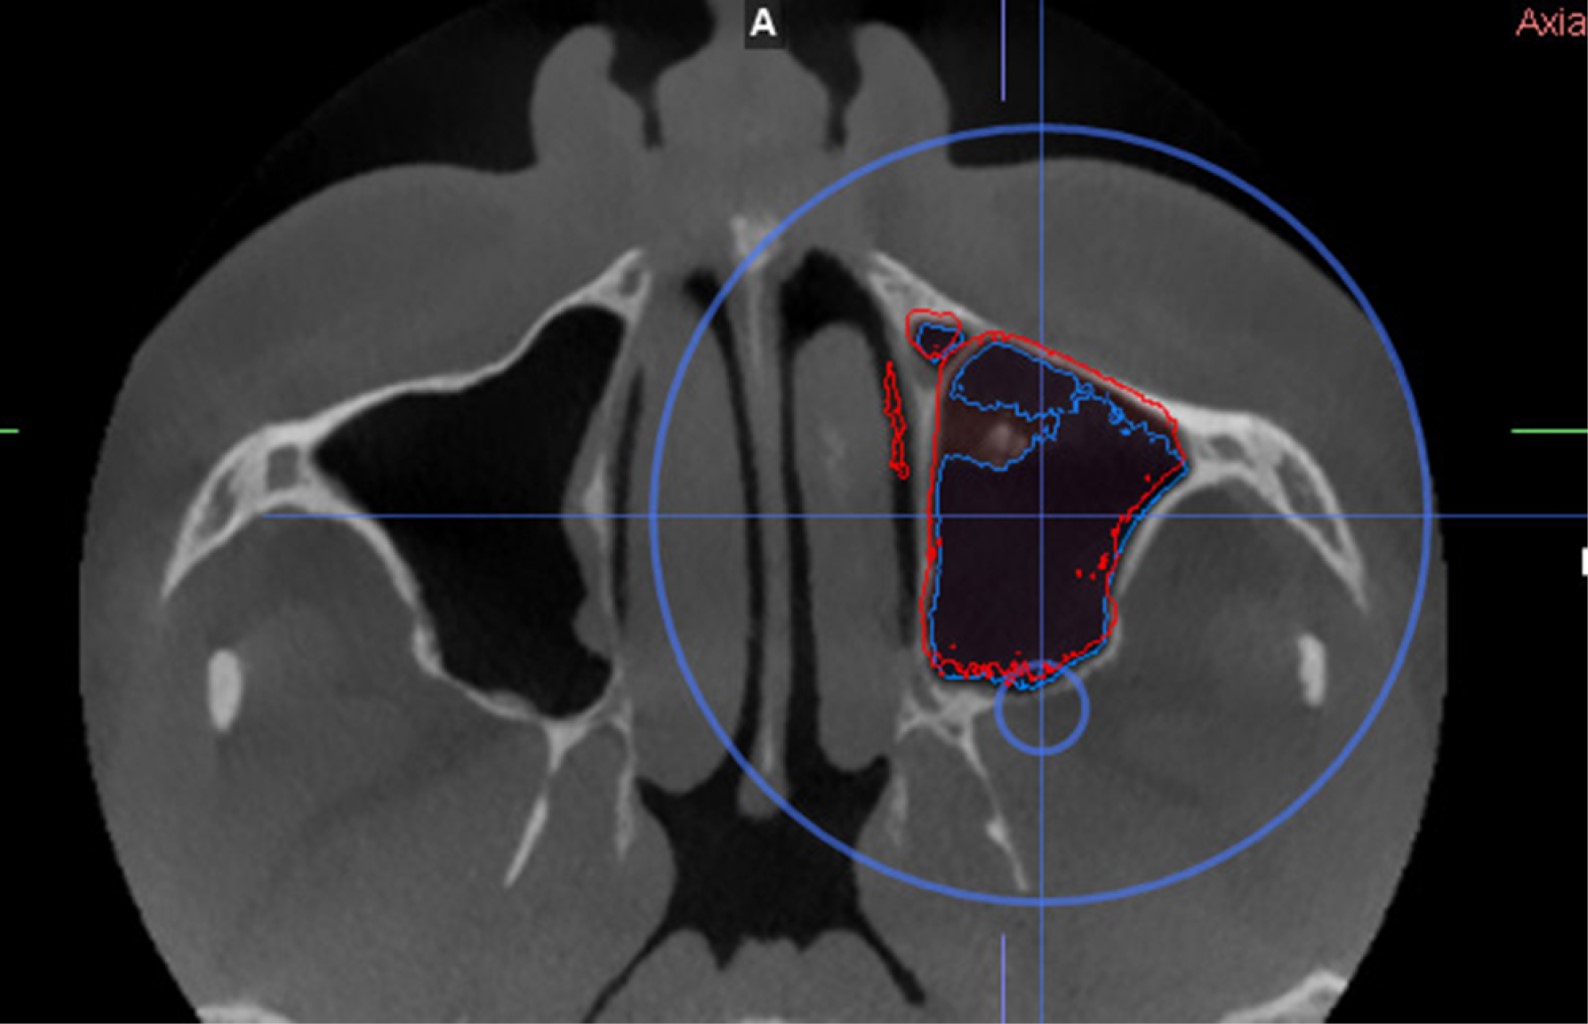

Figure 1